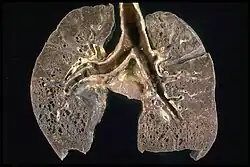

Gross pathology image showing sarcoidosis with honeycombing: Prominent honeycombing is present in the lower lobes accompanied by fibrosis and some honeycombing in the upper lungs. Honeycombing consists of cystically dilated airways separated by scar tissue resembling the honeycomb of bees. It is a nonspecific end stage of many types of interstitial lung disease.

The disease can remit spontaneously or become chronic, with exacerbations and remissions. In some cases, it can progress to pulmonary fibrosis and death. In benign cases, remission can occur in 24 to 36 months without treatment but regular follow ups are required. Some cases, however, may persist several decades.[19] Two-thirds of people with the condition achieve a remission within 10 years of the diagnosis.[144] When the heart is involved, the prognosis is generally less favourable, though corticosteroids appear effective in improving AV conduction.[145][146] The prognosis tends to be less favourable in African Americans than in white Americans.[26] In a Swedish population-based analysis, the majority of cases who did not have severe disease at diagnosis had comparable mortality to the general population.[147] The risk for premature death was markedly (2.3-fold) increased compared to the general population for a smaller group of cases with severe disease at diagnosis.[147] Serious infections, sometimes multiple during the course of disease, and heart failure might contribute to the higher risk of early death in some patients with sarcoidosis.[148][149]